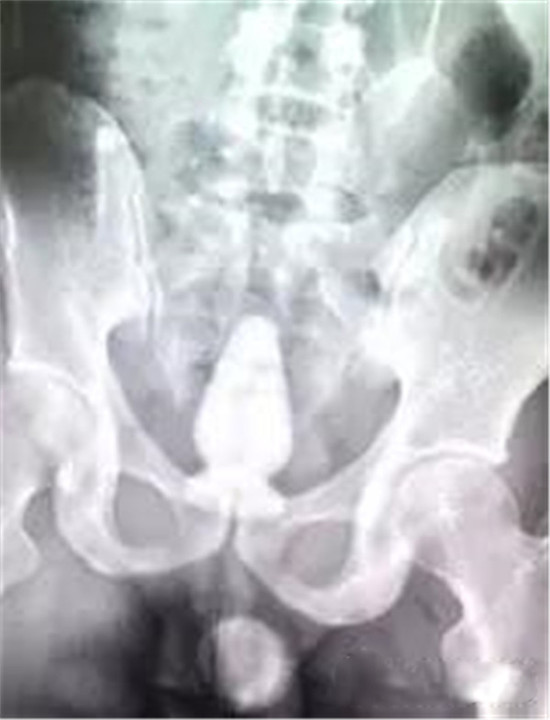

像不像陀螺?

这是一个专门用于肛门自慰的性用品—肛塞。主人把它塞得太里面了。